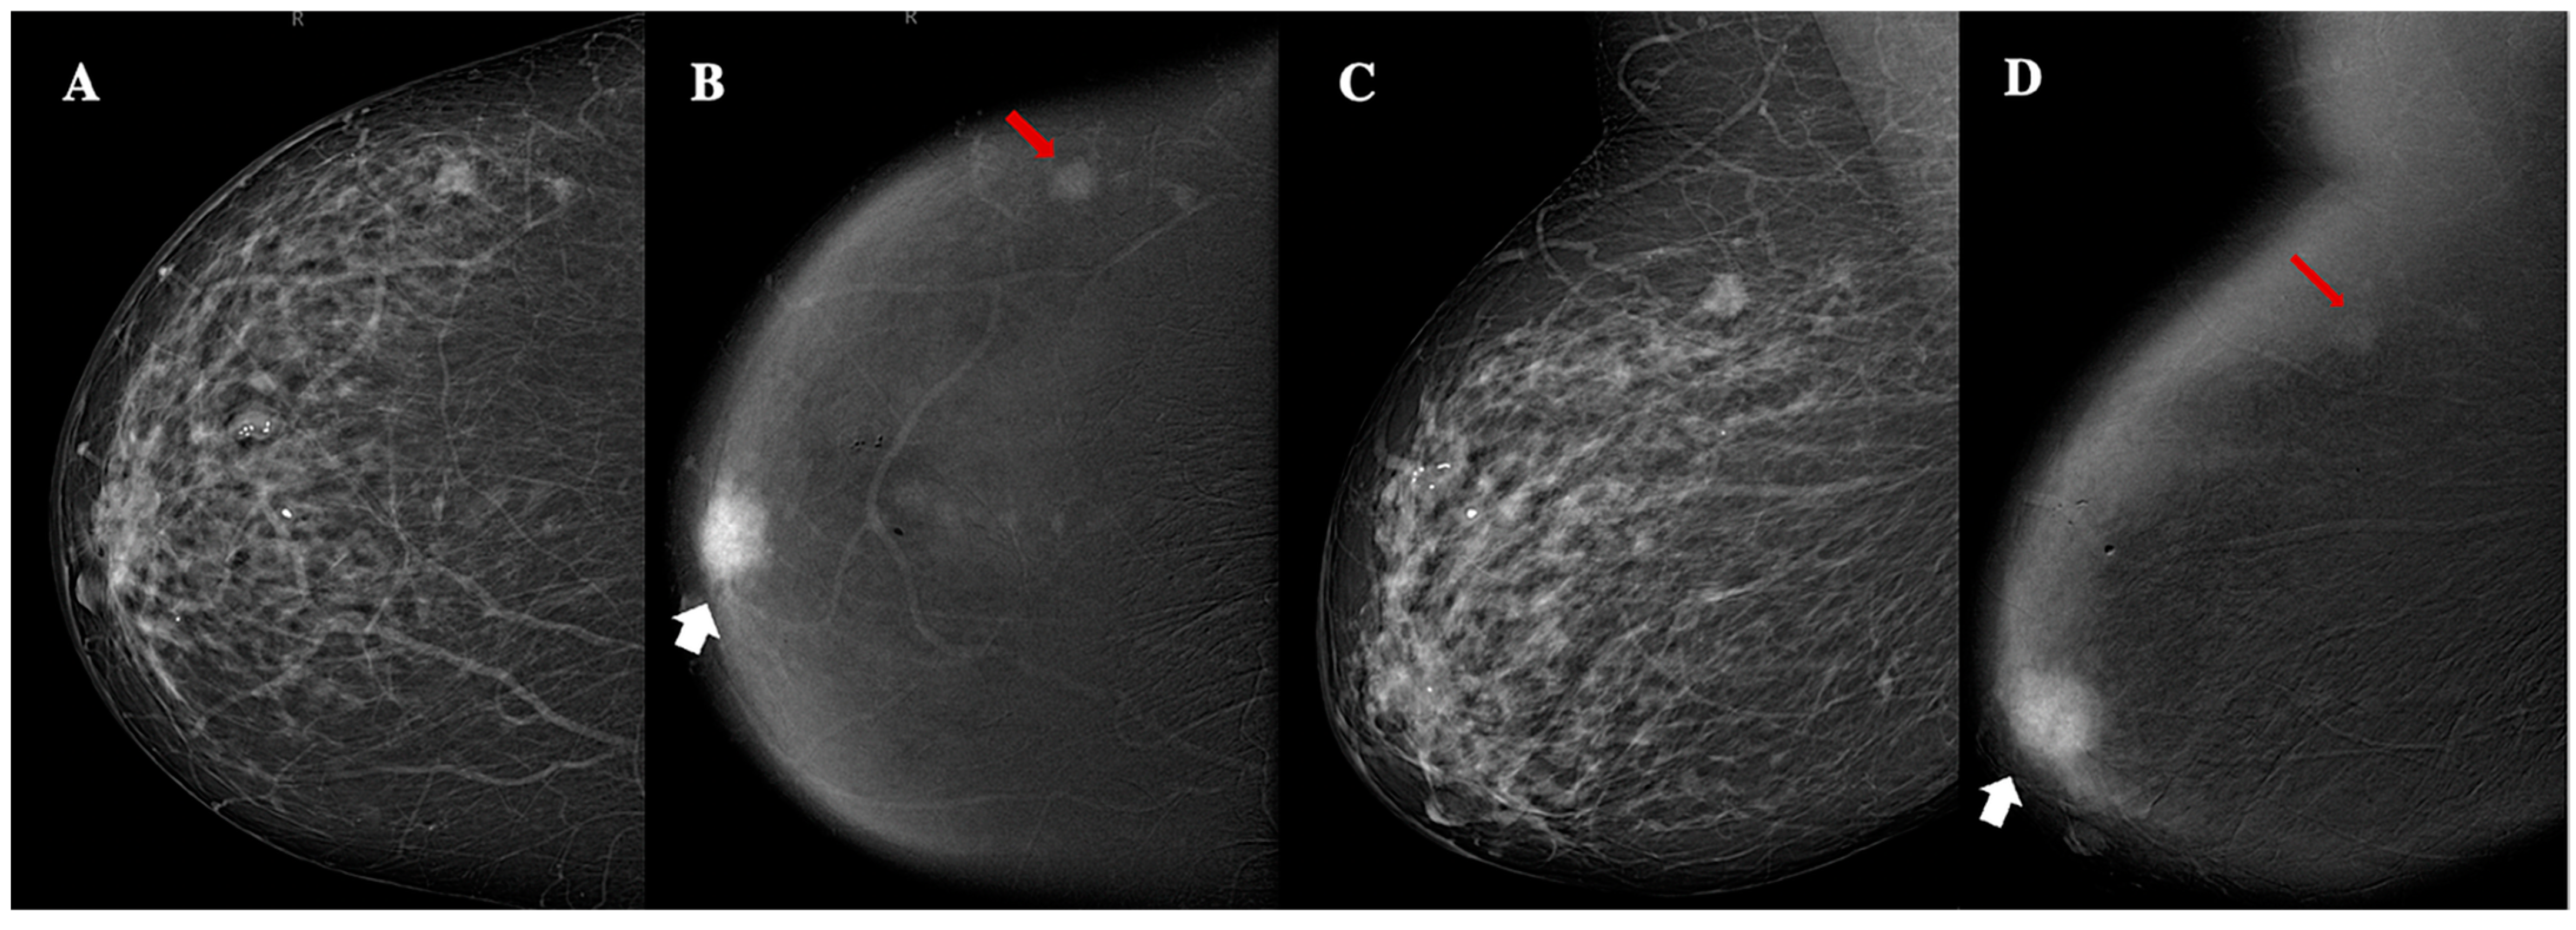

| Lesion shape | Oval (n, %)/round (n, %)/irregular (n,%) | 31 (62%)/9 (18%)/10 (20%) |

| Lesion margins | NC (n, %)/C (n, %) | 7 (14%)/43 (86%) |

| Lesion internal enhancement | Homogeneous (n, %) | 8 (16%) |

| Heterogeneous (n, %) | 37 (74%) | |

| Rim enhancement (n, %) | 5 (10%) | |

| Lesion enhancement conspicuity | Low (n, %) | 25 (50%) |

| Moderate (n, %) | 10 (20%) | |

| High (n, %) | 15 (30%) | |

| Associated features | Nipple retraction (n, %) | 4 (8%) |

| Nipple invasion (n, %) | 2 (4%) | |

| Skin retraction (n, %) | 2 (4%) | |

| Skin thickening (n, %) | 3 (6%) | |

| Skin invasion (n, %) | 9 (18%) | |

| Axillary adenopathy (n, %) | 3 (6%) | |